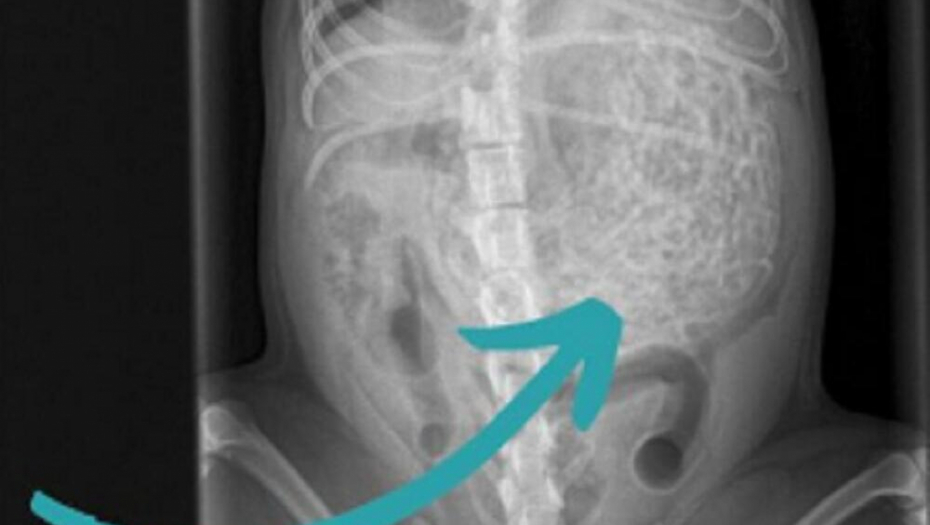

Britanska porodica doživela je pravi šok kada su psa odveli kod veterinara zbog "lošeg osećaja" koji su imali, jer je odjednom postao tih. Tamo je na ultrazvuku otkriveno da je pas pojeo 200 grama gumica za kosu!

Pregled u veterinarskoj ordinaciji pokazao je da pas ima nešto neobično u stomaku, pa su se odmah odlučili na operaciju. Izvađeno mu je oko 60 gumica teških 200 grama, a pas Hem je težak samo šest kilograma.